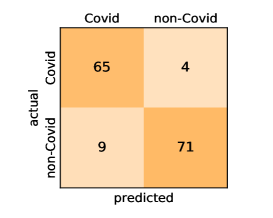

Here, we present and discuss the obtained results for detecting COVID-19 on the considered CT image datasets with different deep networks. We report the quantitative results along with the confusion matrices for every single architecture of the adopted networks.

On the SARS-CoV-2 CT dataset, ResNet101 achieves the best overall performance with respect to almost all evaluation metrics, with an average accuracy and F1-score of and , respectively. The model also achieves an average sensitivity rate of indicating that, on average, only two COVID-19 images are falsely predicted as negatives. It is also powerful enough to correctly identify all Non-COVID-19 cases with only one false positive resulting a specificity rate of . The highest sensitivity score of is achieved by the InceptionV3 model, where only one COVID-19 image is falsely predicted as negative on average. The SqueezeNet model obtains the lowest performance with respect to all evaluation metrics with a fairly acceptable average accuracy and sensitivity scores of and , respectively. Also the ShuffleNet architecture obtains satisfactory performance with approximately improvements on average for all metrics compared with SqueezeNet. Although the results obtained by these models are inferior compared with the rest of models, but they are more efficient. This matches their main objective of reducing the computational costs rather than improving their visual recognition abilities. The rest of models achieve competitive performance and very promising results with slight performance differences. Comparing the different variants of ResNet and DenseNet, we can see that the deeper variants from each architecture yield a slightly better performance. The deeper ResNet101 and ResNeXt101 show a marginal gain in performance compared with their shallower counterparts. The details about class-wise results for each model are summarized in the confusion matrices in Figure 9.